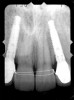

Periapical radiographs were taken to help determine the mesial-distal inclinations of the adjacent tooth roots (Figure 1). The radiographs revealed a serious issue, convergent roots for the right canine and right central, which eliminated that area as a potential implant-receptor site. The space between the left central and canine teeth was minimal, although the roots were relatively parallel. Clinical examination (manual palpation of the root eminences superiorly to the vestibule on the right side) confirmed the root convergence (Figure 2A). The flat, wide zone of the keratinized tissue and lack of interdental papilla was evident for the missing right lateral incisor. There was a marked difference in clinical appearance for the left lateral, which could impact the eventual plan of treatment (Figure 2B). Other significant clinical findings included bilateral facial bone concavities, which existed as a result of the congenitally missing tooth roots. As a diagnostic cue to the underlying bone topography, it is important to follow the demarcation between attached and unattached gingival tissue, and note the crestal width of the available keratinized tissue (Figure 2C).

Figure 1  Pretreatment radiographs revealed convergent roots for the right canine and right central.

Figure 1